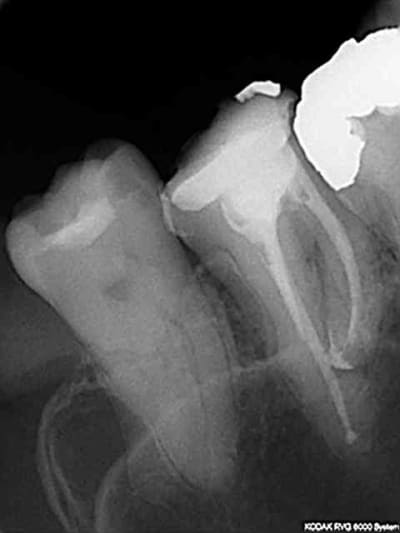

Ca m'arrive de foirer mais rarement, ici racine distale de 16 manque 2 mm. je n'essaie pas de forcer outre mesure et d'arriver à tout prix à l'apex.

Capture d e cran 2015 07 30 16.30 - Eugenol

J'en étais resté au thermocompactage: simple, rapide et pas cher et utilisable avec de la gutta "low cost" genre R&S.

Inconvénient: il faut impérativement faire un cône d'arrêt à LT-1 et avoir un bon tug back à cette longueur sinon c'est le dépassement assuré.

Il y a parfois des casses de pointes de Mc Spadden comme sur la radio de la 14 mais comme c'est un instrument stérile noyé dans de la gutta ça ne (me) pose pas de problème.